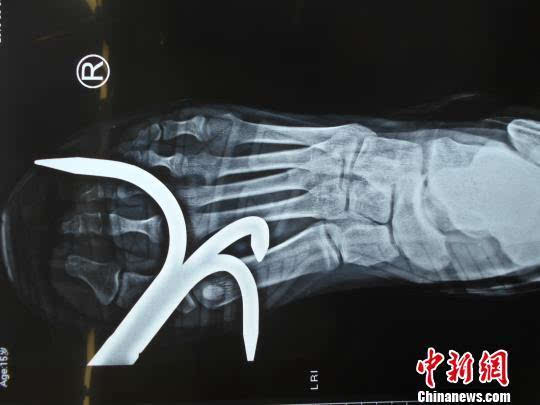

在进行这一环节的过程中,洋洋顺利的用钩子钩住了另一条船,并拉近船的距离。谁料,洋洋跳过去的时候没有估算好位置,一脚踩在了之前扔过来的铁钩上。铁器瞬间扎穿洋洋的脚掌,连带着洋洋穿着的运动鞋卡在了一起。洋洋直接倒在地上站不起来,同学急忙喊人过来帮忙。“密室逃脱”场所的相关负责人闻讯赶到,将洋洋送医急救。

为洋洋治疗的主治医生介绍,因为钩子较大,将鞋子卡住,看不清具体情况,只能用剪刀将鞋子剪碎。随后,洋洋被紧急送到手术室进行手术。经过四个多小时的手术,钩子被取了出来。